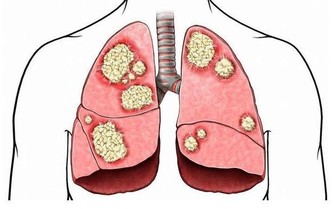

若體內尿酸太多,形成結晶鹽,沉積在腎臟,腎臟長期處在慢性炎症的刺激中,便會功能下降。

腎臟功能一旦受損,排泄廢物(包括尿酸)的能力下降,反過來又會使尿酸水平進一步升高,腎功能進一步受損,形成惡性循環。

不僅如此,沉積的尿酸還可能形成結石,誘發腎絞痛、血尿、腎盂腎炎等。較大的腎結石還可能形成梗阻、腎積水,進一步損傷腎功能。

以上提到的習慣,都可能引起腎單位損傷、腎功能不斷惡化。

其最終結果,就是導致腎臟基本功能喪失,機體內代謝廢物的排泄以及水、電解質和酸鹼平衡等調節出現嚴重障礙,這就是醫學上所說的尿毒症。